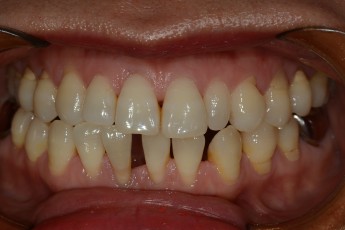

Before

After